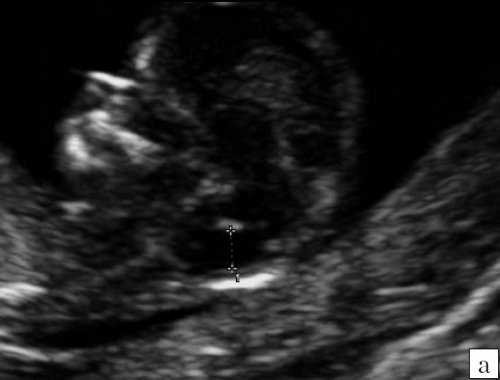

Анализ сохраненных трехмерных изображений позволил получить более детальные характеристики структур мозга плодов с РЭС. На среднесагиттальном срезе в наблюдениях 1, 2 и 4 (в наблюдении 3 получить качественно этот срез не удалось) отмечено наличие атипичной полукруглой формы шатра (fastigium) 4-го желудочка, гипоэхогенная структура мозжечка с контрастирующим наружным контуром (рис. 3). При этом в первых трех наблюдениях отмечено полное отсутствие структур червя, тогда как в наблюдении 4 по контуру 4-го желудочка выявлены гиперэхогенные структуры, расцененные как передние отделы червя. Наличие передних отделов червя отражает и ряд послойных срезов в режиме TUI (рис. 4). У плода в наблюдении 4 также обращает на себя внимание относительное расширение надмозжечковой цистерны, с линейными структурами, при нормальной ориентации намета мозжечка (рис. 4).

а) Наблюдение 2, 3D. На эхограмме: 1 - боковой желудочек, 3v - 3-й желудочек, стрелки - контур мозжечка, пунктирная линия - шатер.

б) Наблюдение 4. На эхограмме: М - мозжечок.